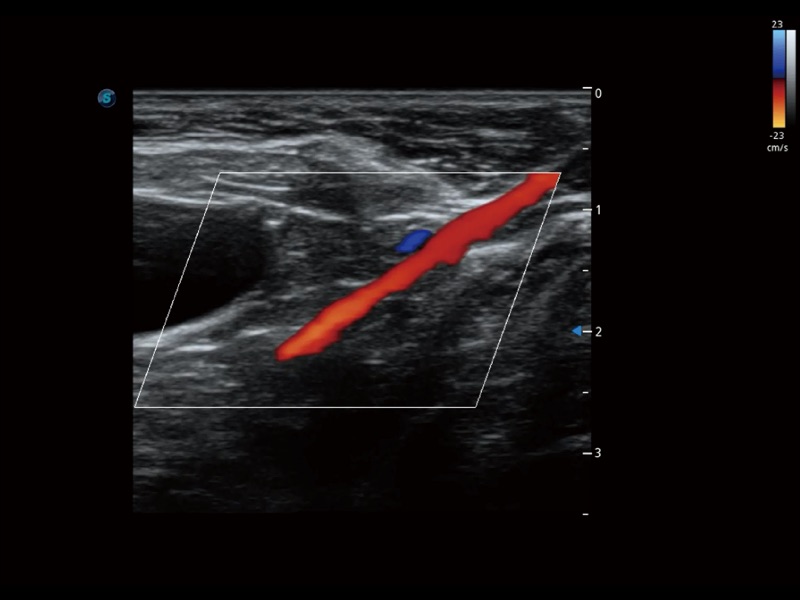

(犬)髂动脉血流

通过色彩血流和实时宽景相结合,可观察到完整的静脉或动脉的血流,方便医生检查。实时扫查过程中,如有任何操作失误也可以很容易地进行回扫擦除,而不会中断扫查。